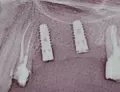

• К сожалению, ваш снимок неинформативен, но по снимку можно предположить, что импланты оголены и скорее всего, их нужно удалить и через 2 месяца установить снова. Ничего страшного в этом нет. Нужно сделать более точный снимок КЛКТ, на котором будет видно состояние вашей костной ткани.